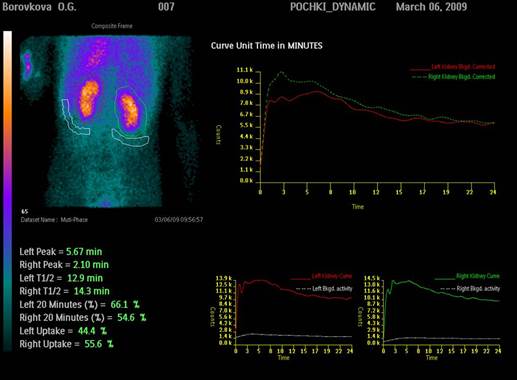

Радионуклидное исследование почек

Чаще всего используются три методики исследования функционального состояние почек: ренография, статическая и динамическая визуализация почек. Реже проводят радионуклидную ангиографию почек и определение ренина. В настоящее время является одним из наиболее рутинных методов исследования. Достоинства этого метода заключаются в том, что он позволяет оценивать как суммарную, так и функцию каждой почки в отдельности, дает низкую лучевую нагрузку и не несет неудобств для больного, может проводиться неоднократно, что важно для контроля за проводимым лечением. Попутно при проведении ренографии можно определять эффективный почечный плазмоток.

Методика исследования. Ренография проводится на трех- или четырехканальных радиографах. Специальной подготовки не требуется. Единственным условием является, чтобы пациенты не были натощак, Положение пациента сидя или лежа на животе. Одноканальные коллимированные датчики устанавливаются: 1 - над областью сердца или венозного сигмовидного синуса, 2 и 3 - над областью почек, 4 - над мочевым пузырем. Установка датчиков над областью почек производится по обзорным рентгенограммам или анатомическим ориентирам (центр датчика на середину 12 ребра). Для исследования применяют гиппуран (меченный йодом 131-для детей - меченный йодом 125) или ДТПА, меченое иттербием-169 или технецием-99м, которые вводят внутривенно после установки датчиков. Гиппуран экскретируется в дистальных отделах канальцев, ДТПА выводится из крови за счет клубочковой фильтрации. На ренограмме можно выделить три сегмента. Первый - сосудистый - характеризуется быстрым подъемом кривой и отражает в основном поступление препарата в кровеносное русло почки и околопочечной клетчатки. Второй- секреторный - подъем кривой более медленный отражает преобладание поступления препарата в почку над выведением. Третий - экскреторный. - спад кривой отражает преобладание выведения препарата из почки над поступлением. Следует учитывать, что названия сегментов даны условно, так как поступление препарата в кровеносное русло почки, его секреция и экскреция происходят одновременно. Если на кривой можно выделить все три сегмента, то такая кривая носит название функционального типа. В этом случае для отличия нормы от патологии требуется рассчитать ряд временных, относительных и амплитудных показателей. Наиболее часто рассчитываются такие временные параметры, как время достижения максимума (Тмакс.) и время полувыведения (Т1/2) препарата. Тмакс. рассчитывается от сосудистой фазы до пика, а Т1/2 от пика до снижения кривой наполовину его высоты. В норме Тмакс. не должно превышать 4 минут, Т1/2 - 8 минут. Кроме того, имеются кривые, на которых нельзя выделить все три сегмента. Такие кривые подлежат только качественной оценке. К ним относятся: